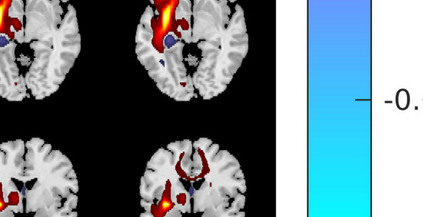

In the last two decades, unsupervised latent variable models---blind source separation (BSS) especially---have enjoyed a strong reputation for the interpretable features they produce. Seldom do these models combine the rich diversity of information available in multiple datasets. Multidatasets, on the other hand, yield joint solutions otherwise unavailable in isolation, with a potential for pivotal insights into complex systems. To take advantage of the complex multidimensional subspace structures that capture underlying modes of shared and unique variability across and within datasets, we present a direct, principled approach to multidataset combination. We design a new method called multidataset independent subspace analysis (MISA) that leverages joint information from multiple heterogeneous datasets in a flexible and synergistic fashion. Methodological innovations exploiting the Kotz distribution for subspace modeling in conjunction with a novel combinatorial optimization for evasion of local minima enable MISA to produce a robust generalization of independent component analysis (ICA), independent vector analysis (IVA), and independent subspace analysis (ISA) in a single unified model. We highlight the utility of MISA for multimodal information fusion, including sample-poor regimes and low signal-to-noise ratio scenarios, promoting novel applications in both unimodal and multimodal brain imaging data.